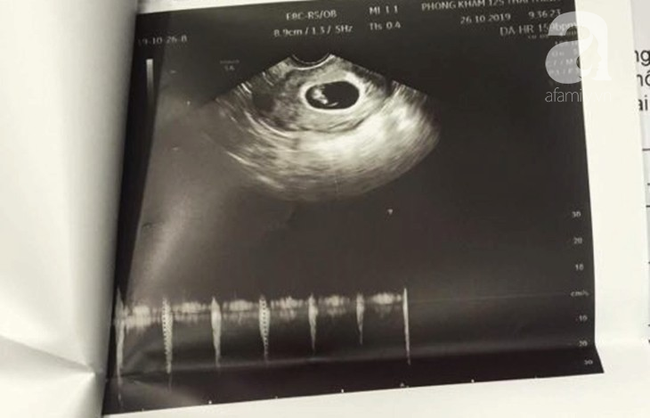

Đến ngày 27/10, chị A. cùng người thân đến thẩm mỹ viện Sophie International thông báo đã mang thai 8 tuần. Hôm sau, chị được đại diện thẩm mỹ đưa đến Bệnh viện AIH (quận 2) tiến hành thăm khám.

Phía AIH xác nhận bệnh nhân có thai, tuy nhiên cho biết với tuần thai trong khoảng 4 tuần rất khó phát hiện thai kỳ dù đã siêu âm, kiểm tra. Lúc này, chị A. và người thân có lời nói xúc phạm đến bác sĩ khám.